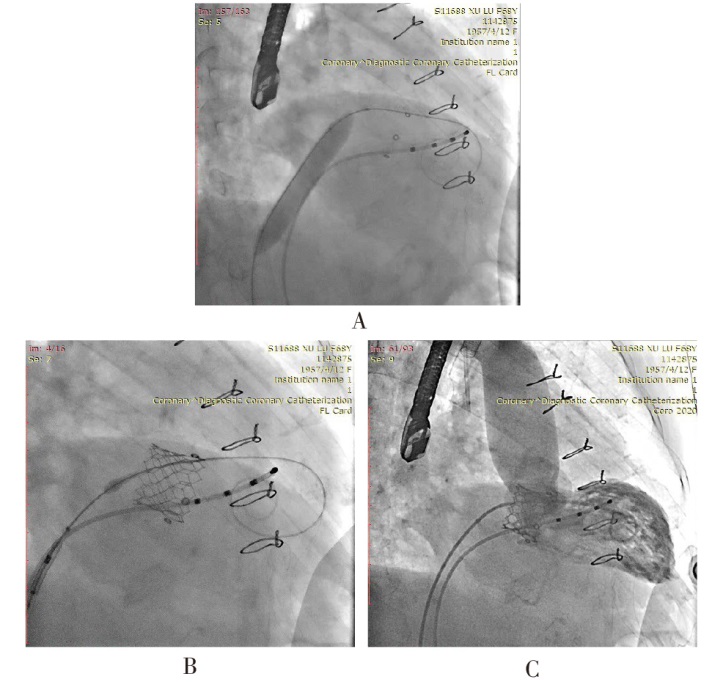

目的 评估经导管二尖瓣“瓣中瓣”置换术(ViV-TMVR)治疗人工二尖瓣生物瓣衰败的安全性和有效性。方法 选取17例因二尖瓣生物瓣衰败需行ViV-TMVR的患者,收集患者的年龄、性别、体质量指数(BMI)、二尖瓣生物瓣使用年限,合并症(高血压、冠心病、陈旧性脑梗死、心房颤动、糖尿病),美国纽约心脏病学会(NYHA)心功能分级;术前超声心动图评估左心室舒张末期内径(LVEDD)、右心房内径(RA)、肺动脉收缩压(PASP)、左心室射血分数(LVEF),二尖瓣生物瓣衰败类型,二尖瓣生物瓣反流程度、狭窄程度,术前生物瓣峰值流速、平均跨瓣压差,三尖瓣反流程度;美国胸外科医师协会(STS)评分;术中穿刺路径、瓣膜类型、术中并发症、手术时间、术后即刻经食管超声心动图(TEE)评估(瓣中瓣峰值流速、瓣中瓣平均跨瓣压差、瓣中瓣反流或瓣周反流);术后进入重症监护室(ICU)/心血管内科重症监护室(CCU)的时间,术后住院时间,以及术后30 d超声心动图复查结果,NYHA心功能分级。根据使用瓣膜不同分为国产纽脉瓣膜组(国产组,10例)与进口爱德华瓣膜组(进口组,7例)。分析ViV-TMVR的安全性和有效性,并对比国产瓣膜和进口瓣膜的效果。结果 17例患者均成功通过穿刺房间隔途径接受ViV-TMVR治疗,且未发生严重并发症,术后30 d再住院率为0。国产组与进口组手术时间、瓣中瓣瓣周轻度反流、术后即刻及术后30 d瓣中瓣峰值流速、术后即刻及术后30 d瓣中瓣平均跨瓣压差、术后ICU/CCU监护时间、术后住院时间,术后30 d NYHA心功能Ⅲ—Ⅳ级患者占比差异无统计学意义。术后30 d随访中1例患者因脑出血死亡,主要不良心血管事件(MACE)为脑出血1例。相较于术前,术后即刻及术后30 d瓣中瓣峰值流速、瓣中瓣平均跨瓣压差、LVEF、PASP下降;相较于术后即刻,术后30 d瓣中瓣峰值流速、平均跨瓣压差升高(P<0.01),LVEF、PASP差异无统计学意义。结论 经房间隔穿刺ViV-TMVR对于生物瓣衰败患者短期安全且有效,且国产瓣膜与进口瓣膜疗效相当。

Objective To evaluate the safety and efficacy of transcatheter mitral valve-in-valve replacement (ViV-TMVR) in the treatment of bioprosthetic mitral valve failure. Methods Seventeen patients with bioprosthetic mitral valve failure who required ViV-TMVR were selected. Preoperative data including age, gender, body mass index (BMI), usage time of bioprosthetic mitral valve, comorbidities (hypertension, coronary heart disease, old cerebral infarction, atrial fibrillation and diabetes) and New York Heart Association (NYHA) functional class were recorded, and left ventricular end-diastolic diameter (LVEDD), right atrial diameter (RA), pulmonary artery systolic pressure (PASP), left ventricular ejection fraction (LVEF), type of bioprosthetic mitral valve failure, degree of bioprosthetic mitral valve regurgitation and stenosis, peak velocity and mean transvalvular pressure gradient of the bioprosthetic mitral valve, and Society of Thoracic Surgeons (STS) score were also collected. Intraoperative data included puncture route, valve type, intraoperative complications, operation time and immediate postoperative transesophageal echocardiography (TEE) assessment (peak velocity and mean transvalvular pressure gradient of the valve-in-valve, valve-in-valve regurgitation or paravalvular regurgitation) were collected. Postoperative data included time in the intensive care unit (ICU)/cardiovascular intensive care unit (CCU), total postoperative hospital stay and 30-day postoperative echocardiographic results and NYHA functional class were recorded. Patients were divided into the domestic NewMed valve group (10 cases) and the imported Edwards valve group (7 cases) based on the type of valve used. The safety and efficacy of ViV-TMVR were analyzed, and the efficacy of domestic valves and imported valves was compared. Results All 17 patients successfully underwent ViV-TMVR via the transseptal approach without serious complications, and the 30-day readmission rate was 0%. There were no significant differences in operation time of domestic valves and imported valves, mild paravalvular regurgitation of the valve-in-valve, peak velocity and mean transvalvular pressure gradient of the valve-in-valve immediately after surgery and at 30-day postoperatively, time in ICU/CCU, total postoperative hospital stay and the proportion of patients with NYHA functional class Ⅲ-Ⅳ at 30-day postoperatively between the domestic valve group and the imported valve group. During the 30-day follow-up, one patient died of cerebral hemorrhage, and one patient had major adverse cardiovascular events (MACE, cerebral hemorrhage). Compared with before the operation, the peak velocity and mean transvalvular pressure gradient of the valve-in-valve, LVEF, and PASP decreased immediately after surgery and at 30 days after surgery. Compared with immediately after surgery, the peak velocity and mean transvalvular pressure gradient of the valve-in-valve increased at 30 days postoperatively (P < 0.01), while there were no significant differences in LVEF and PASP. Conclusion Transseptal ViV-TMVR is safe and effective in the short term for patients with bioprosthetic mitral valve failure who are at high risk of re-thoracotomy, and the efficacy of domestic valves is comparable to that of imported valves.